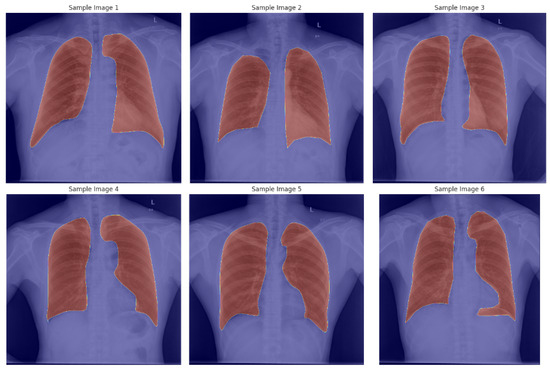

- Rajaraman, S.; Yang, F.; Zamzmi, G.; Xue, Z.; Antani, S.K. Generalizability of Deep Adult Lung Segmentation Models to the Pediatric Population: A Retrospective Study. arXiv 2022, arXiv:2211.02475. [Google Scholar]